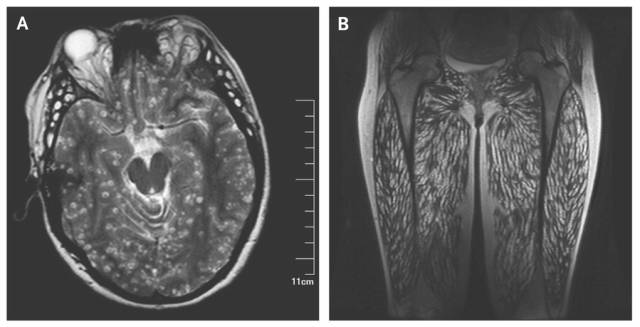

猪囊虫

有囊虫的猪肉为"米肉",或者是称"豆肉"。

一名云南女子,因长期食用生的猪肉,致使全身长满了寄生虫,我的天啊...小编表示被吓到了......

猪囊尾蚴病又称猪囊虫病,俗称囊虫病,有囊虫的猪肉为"米肉",或称"豆肉"。是由猪带绦虫幼虫寄生于人或猪、野猪等中间宿主引起人畜共患的寄生虫病。在自然条件下,猪是易感动物。人也可经消化道感染发病。

猪囊虫寄生于人体的肌肉和各组织器官对人的健康产生危害。囊虫病的患者受害情况因囊尾蚴的寄生部位而有所不同,

• 可导致肌肉酸痛、无力、发胀等症状;

• 可引起视力障碍,甚至导致失明;

• 可使人头昏、头疼、记忆力减退,严重的可引起癫痫大发作,甚至失语、昏迷、死亡。

• 体内有成虫寄生的患者主要表现为腹痛、腹泻、消化不良、贫血和消瘦等。